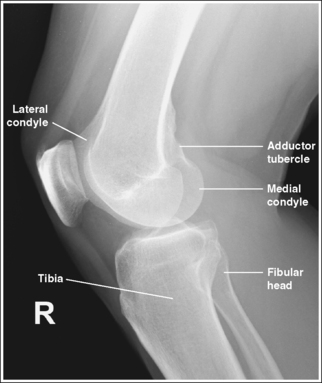

• Distinguishing lateral and medial condyles. The first step you should take when evaluating an image on which the distal condylar surfaces are not aligned is to determine which condyle is the lateral and which is the medial. The most reliable method for identifying the medial condyle is to locate the rounded bony tubercle known as the adductor tubercle. It is located posteriorly on the medial aspect of the femur, just superior to the medial condyle. The size and shape of the tubercle are not identical on every patient, although this surface is considerably different from the same surface on the lateral condyle, which is smooth. Once the adductor tubercle is located, the medial condyle is also identified. Another difference between the medial and lateral condyles is evident on their distal articulating surfaces. The distal surface of the medial condyle is convex, and the distal surface of the lateral condyle is flat.